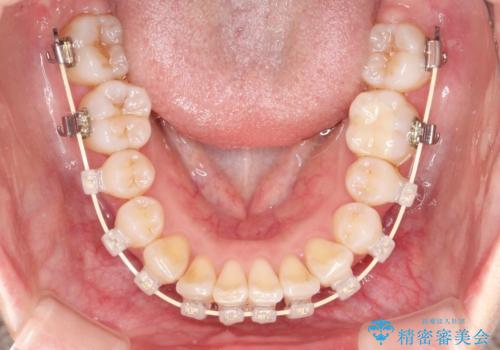

- 矯正装置

- 審美装置

- 治療期間

- 2年1ヶ月

- 治療回数

- 10-30回